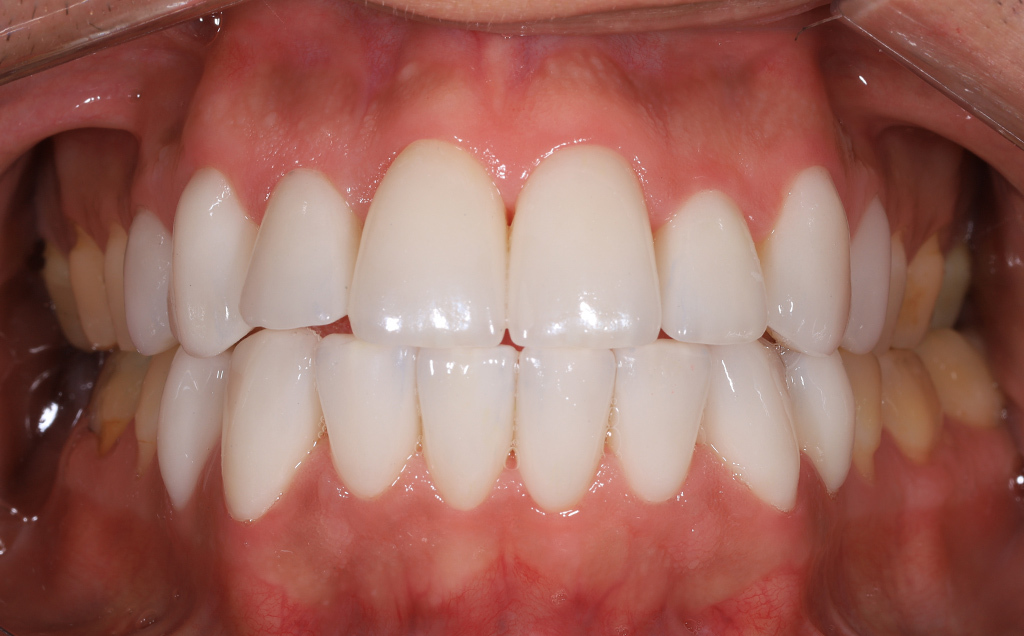

Zaprezentujemy serię poruszających historii pacjentów, którzy zdecydowali się na kompleksowe leczenie dentystyczne. Od przypadków zaawansowanej próchnicy, przez wypadki, które wymagały rekonstrukcji zębów, po pacjentów marzących o hollywoodzkim uśmiechu dzięki zastosowaniu licówek – każda historia jest dowodem na to, jak nowoczesna stomatologia może odmienić życie.

Skupimy się na innowacyjnych technologiach i metodach leczenia stosowanych w naszej klinice, które sprawiają, że te metamorfozy są możliwe. Od cyfrowego projektowania uśmiechu (DSD), przez ortodoncję i implanty, po zaawansowaną chirurgię szczękowo-twarzową. Omówimy, jak te techniki pracują razem, aby osiągnąć najlepsze wyniki.